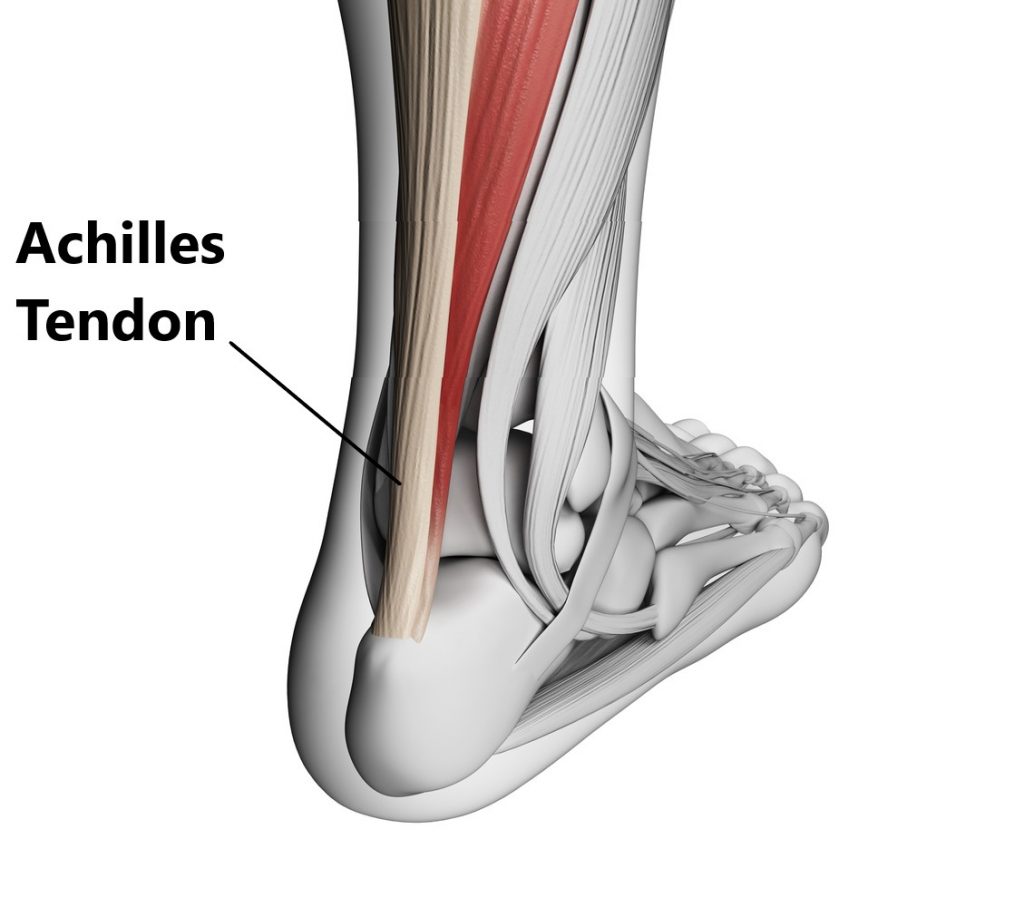

pictures of achilles tendon

Achilles Tendon – Squat University

Achilles Tendon Diagram – 1000+ images about medical anatomy on …